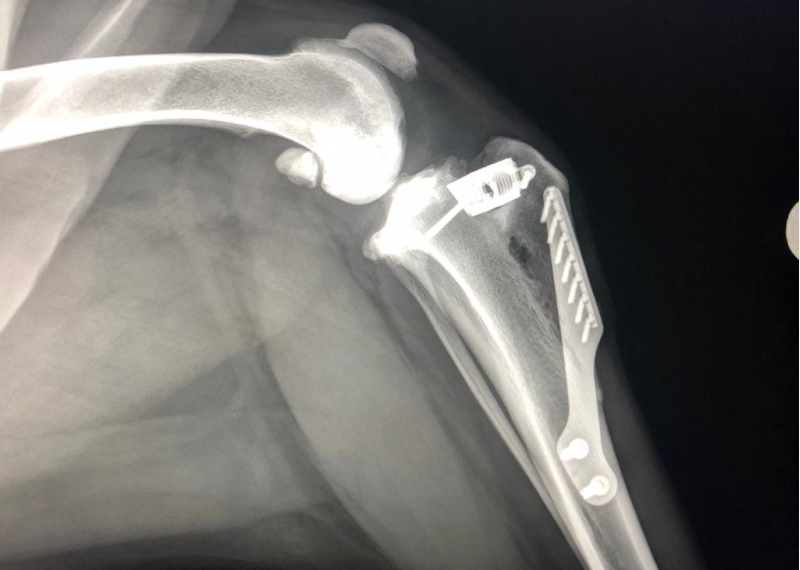

Botbreuken en orthopedische chirurgie

Afhankelijk van de aard van de botbreuk, de leeftijd en het gewicht van uw dier zijn er vaak meer manieren om het herstel ervan te garanderen. Dit hoeft zelfs geen chirurgische te zijn. Het varieert van hokrust tot gecompliceerde chirurgie door een erkend specialist. Bij eenvoudige breuken kunnen wij soms zelf een pin in het bot inbrengen. In overleg met u wordt besproken wat voor u en uw dier de beste oplossing is. Wilt u meer weten? Neem dan contact met ons op!